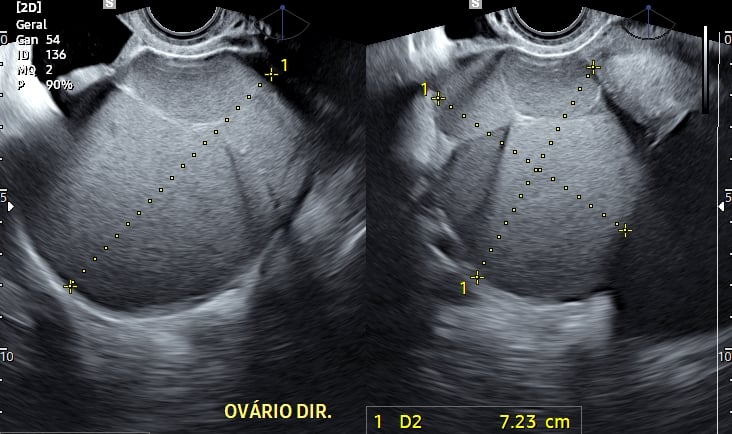

Ovários e útero: identificação de cistos endometrióticos e alterações morfológicas.